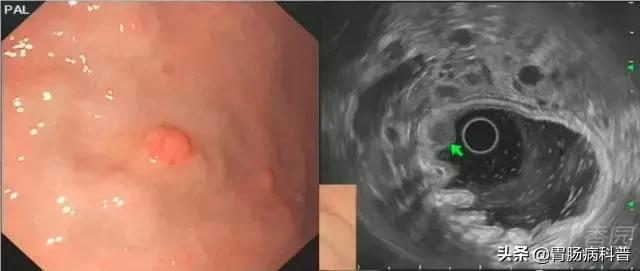

图 1

图 1 A-B 胃体上后壁间质瘤;D-E 胃窦前壁间质瘤,以上病变均起源于黏膜第四层,与周围黏膜界线清晰,与肌层延续处可观察到「喇叭口」样结构(箭头所示)